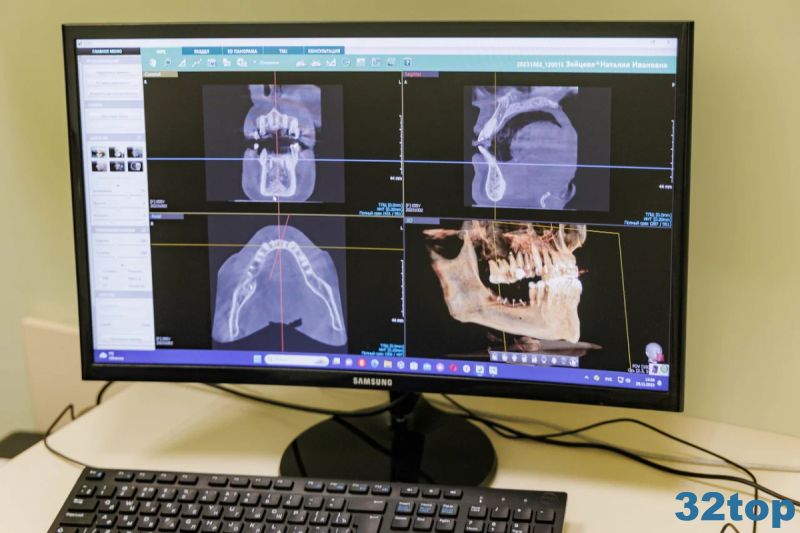

Примеры работ